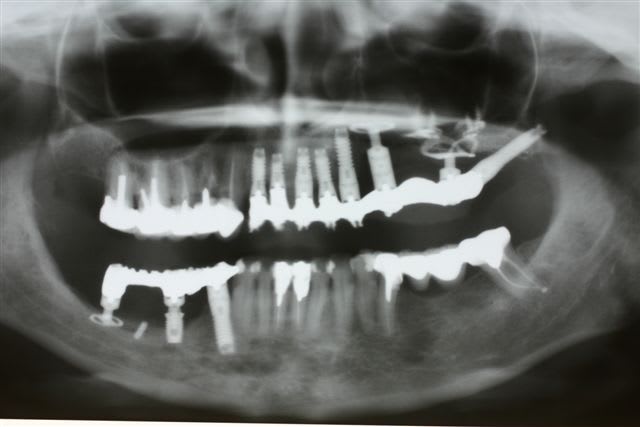

1 Radiographie panoramique avant implantation.

Les deux implants du haut ont été perdus.

2La greffe autologue prélevée à la hanche à totalement fondu.

Il ne reste que la vis d'ostéosynthèse qui avait servi à fixer le greffon.

3 Radiographie Panoramique de la correction

4 Utilisation d'un implant à plaque.

La vis d'ostéosyntèse impossible à dévisser a dû être coupée.